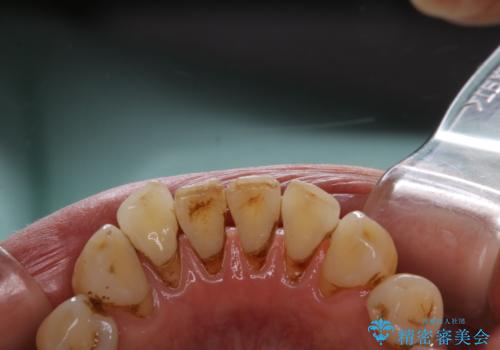

- クリーニングがかなり久しぶりで、全体的にきれいにして欲しいとのことで来院されました。全体的にステインの量がとても多かったため、施術前にご相談をし、60分コースでできる限りのステイン落としを行うこととなりました。今回は審美的に見える表側をメインでPMTCを行いました。

毎日丁寧に歯磨きをしていても、日常生活での飲食物などにより着色してしまうことはあります。PMTCでは、歯の表面の凸凹にミネラルを補給して、ツルツルの表面に仕上げます。定期的にPMTCを行うことにより、歯質の強化になり着色がつきにくい状態になります。